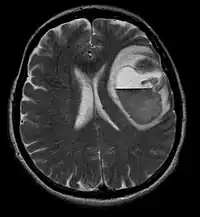

Computertomografi (CT) og magnetisk resonansbilleddannelse (MRI) kan effektivt påvise en neoplasi i hjernen. MR er mere følsom end CT til at identificere læsioner, men har kontraindikationer for patienter med pacemakere, inkompatible proteser, metalclips og andre. CT er fortsat den foretrukne metode til at påvise forkalkninger i læsioner eller knogleerosion af kaloten eller bunden . Brugen af kontrastmidler, som er ioderede i tilfælde af CT og paramagnetiske (gadolinium ) i tilfælde af MR, tillader erhvervelse af information om vaskularisering og integritet af blod-hjerne-barrieren, en bedre definition af den tumorøse tumor sammenlignet til det omgivende ødem og generering af hypoteser om graden af malignitet . Den radiologiske undersøgelse giver også mulighed for en vurdering af de mekaniske virkninger og deraf følgende ændringer i hjernestrukturer som følge af tumoren, såsom hydrocephalus og brok, hvis virkninger kan være dødelige. Til sidst, som forberedelse til operation, kan denne diagnostik bruges til at bestemme placeringen af læsionen eller infiltrationen af tumoren i vitale områder af hjernen. Til dette formål er MR mere effektiv end CT, fordi den kan give tredimensionelle billeder.

På-MRI viser en intrakraniel tumor som en massiv læsion, der kan blive mere selvlysende efter brug af kontrastmidlet. Der er dog altid en signalanomali i-Magnetisk resonansbilleddannelse, som indikerer tilstedeværelsen af neoplasi eller vasogent ødem. Sædvanligvis er øget luminescens (kontrastforbedring) tegn på en tumor af en højere grad af malignitet. En kontrastring er karakteristisk for glioblastom, hvor den selvlysende del svarer til den vitale del af den ondartede tumor, og den mørkere del-hypointense område svarende til vævsnekrose.

Patienter lider af en række karakteristiske symptomer på en fokal eller multifokal massiv læsion. MR viser sædvanligvis tumorer med homogen kontrastforøgelse i den dybe periventrikulære hvide substans. Multifokalitet og inhomogen forbedring er typisk for patienter med et svækket immunsystem. Analyse af CNS-lymfom er ekstremt vigtig i differentialdiagnosen af hjerneneoplasi. Det skal bemærkes, at administration af kortikosteroider kan føre til fuldstændig forsvinden af forstærkningen, hvilket gør diagnosen af læsionerne vanskelig. Hvis CNS-lymfom skal overvejes i differentialdiagnosen, bør kortikosteroider derfor undgås, medmindre masseeffekten forårsager et alvorligt og umiddelbart problem hos patienten.